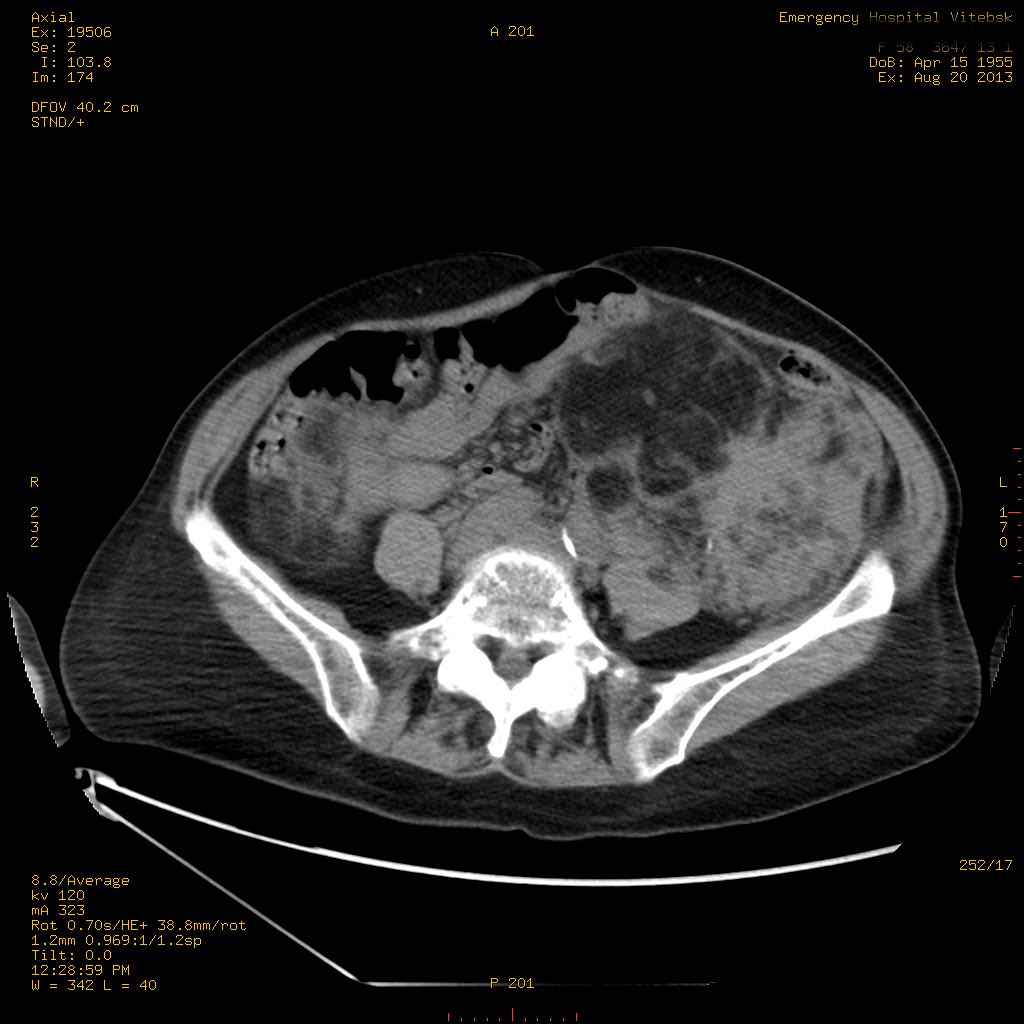

УЗИ почек - туберозный склероз

Пожилая женщина с нормальными мочевиной и креатинином.

Ангиомиолипоматоз почек , думаю компонент туберозного склероза.

Да, туберозный склероз.

Случай консультирован на кафедре радиологии Католического университета г.Лёвен (Бельгия) - зав каф. профессор Р.Оуен.